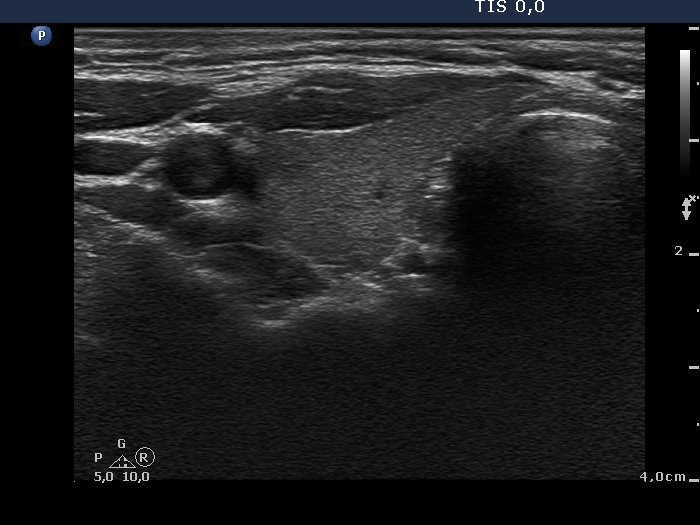

Third examination 24 months after initial investigation (3rd row of images)

Clinical data: The thyrostatic therapy was stopped 13 months ago. The patient had no complaints.

Palpation: unchanged.

Results of blood tests: euthyroidism (TSH 0.52 mIU/L, FT4 14.6 pM/L).

Ultrasonography: The size of the thyroid decreased further. The echo structure and the vascularization became normal.

Suggestion: to check the thyroid function every year, in the event of complaints or pregnancy at once.

Comment. This case demonstrates typical course of non-relapsing Graves disease. The change in hormone levels and in the ultrasound pattern are parallel.